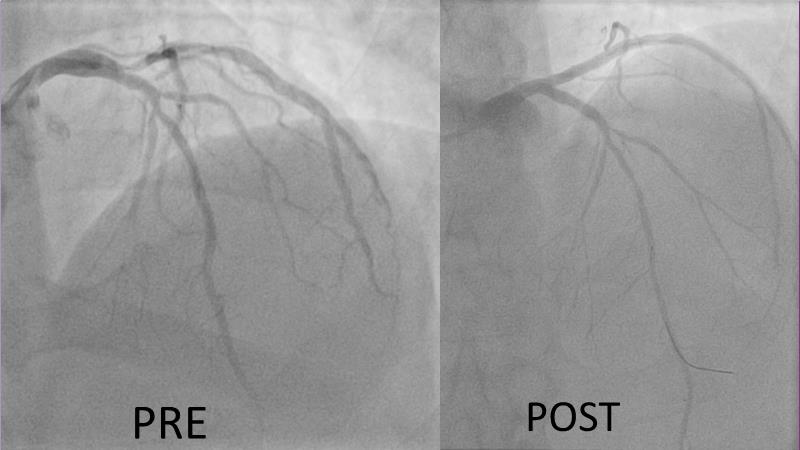

Join this session to explore the advantages of a fully optical approach in optimizing percutaneous coronary intervention (PCI) with the OptoWire III physiology wire and Nipro HF-OCT catheter. Through a practical case, you'll discover the significance of coronary physiology and intravascular imaging in bifurcation PCI and gain insights into how the performance and accuracy of the OptoWire III physiology wire can facilitate fast and reliable decision-making, particularly in side branch jailing scenarios.

- To review, through a practical case, the value of coronary physiology and intravascular imaging in bifurcation PCI

- To understand how the performance and accuracy of OptoWire III physiology wire can make the difference for fast and reliable decision-making in bifurcations, particularly through side branch jailing